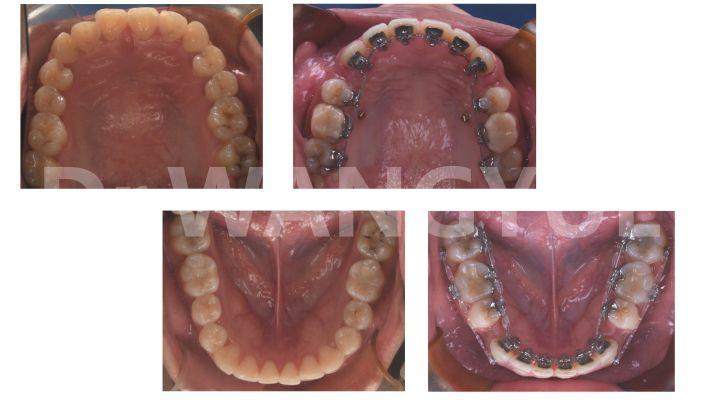

因此,在此契机上,隐形的舌侧固定矫治器成为了满足不断增长的成人正畸调节需求的必需品。

舌侧正畸从外观看是完全隐形的,可以说是比隐形矫正更为隐形。而隐形牙套或者陶瓷制成的牙套,仍然是可见的。这也就是为什么对个人形象要求比较高的职业,例如演员、主持、律师、销售等都选择舌侧牙套。。

舌侧矫正| 拯救齐凸的利器

舌侧内收5个月战报,这是精致ol对侧颜的追求,不变的是整齐,变化的是侧脸的曲线